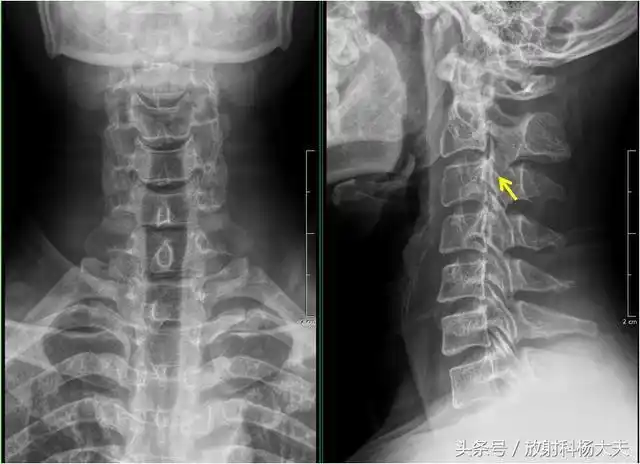

一位经常低头玩手机的女子的颈椎x光照片颈椎曲线变成反弓这危害非常

【健康】x线片诊断这种颈椎病,切勿盲目按摩,有可能导致瘫痪